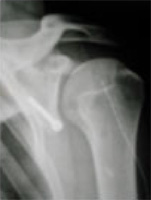

La radiographie est l’examen de base, en sachant que normale, elle n’élimine pas le diagnostic. On y voit souvent les traces des anciennes luxations : une fracture du bord antéro inférieur de la glène, un simple émoussement de celle ci, une encoche à la partie postérieure de la tête humérale signant son impaction lors d’une luxation (encoche de Malgaigne). Les signes cliniques évocateurs suffisent à porter le diagnostic. Une radio de l’épaule luxée lors d’un accident est très utile pour confirmer le diagnostic. Si le tableau est atypique d’autres examens sont utiles :

Rx de la luxation |

On réalise une radiographie standard d’épaule.

Radiographie de l’épaule

Cette radiographie permet de voir l’usure du cartilage et les déformations osseuses liées à l’arthrose : ostéophytes ou géodes (en jaune sur la photo précédente).

La radiographie permet également de confirmer le diagnostic de la cause de l’arthrose (polyarthrite rhumatoïde, nécrose, rupture massive de la coiffe). On réalisera également un scanner dans le cadre d’un bilan préopératoire pour juger de la quantité d’os restant afin d’y implanter une éventuelle prothèse. L’IRM ou arthro-TDM peut-être utile pour juger de la qualité des tendons de la coiffe des rotateurs.

Radio d’une prothèse à l’épaule |